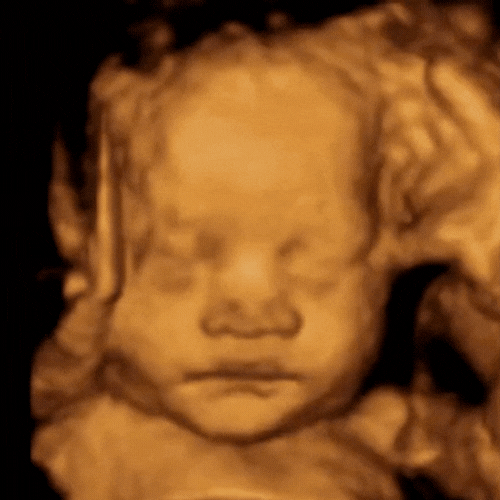

ScanSanctuary Client Scan Examples